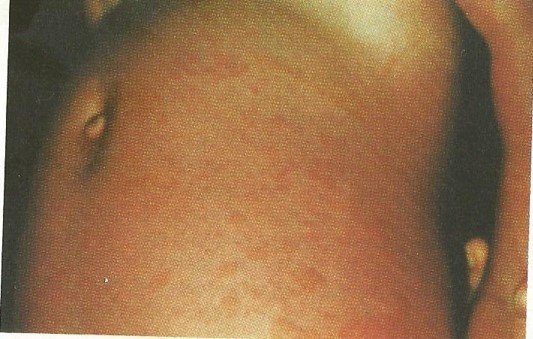

A manifestação clínica da AIJ pode variar de criança para criança, podendo ocorrer sintomas variados, com comprometimento diversos, como pleurite, miocardite, exantema reumatoide, pericardite, hepatoesplenomegalia, linfadenomegalia, por isso, a avaliação pediátrica deve ser criteriosa e o acompanhamento médico deve ser acontecer com um reumatologista pediátrico.

A febre da AIJ, pode preceder o aparecimento da artrite por dias, semanas, meses. Essa febre pode ocorrer a qualquer hora ou dia, em picos, no começo da manhã, final da tarde ou início da noite, muitas vezes vem acompanhada de exantema de pele.